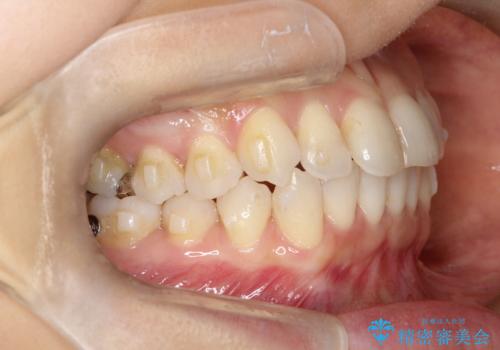

八重歯と前歯のガタガタをインビザラインで

- 八重歯と前歯のガタガタを主訴に来院されました。

目立たず矯正したいとのことでインビザラインで矯正することとしました。

インビザラインで目立たずに治療を終えることができ、喜んでいただけました。